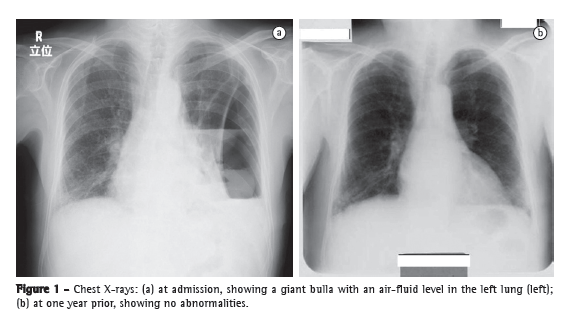

A 79-year-old man sought treatment in the emergency room, complaining of a 3-month history of persistent fever, chest pain, and general fatigue. He had a smoking history of 60 pack-years and had been a heavy drinker of Japanese sake (180 mL/day) for the past thirty years. Laboratory test results indicated severe inflammation, and a chest X-ray showed a giant bulla with a diameter of 24 cm in the left lung (Figure 1a). By his own account, he had no history of abnormalities on X-rays, and his latest medical check-up, conducted in the preceding year, had produced no abnormal findings (Figure 1b). CT scans of the chest revealed that the bulla was fluid-filled and measured 4.5 × 17 × 24 cm (Figure 2). The patient was diagnosed as having a lung abscess and was admitted to our hospital.